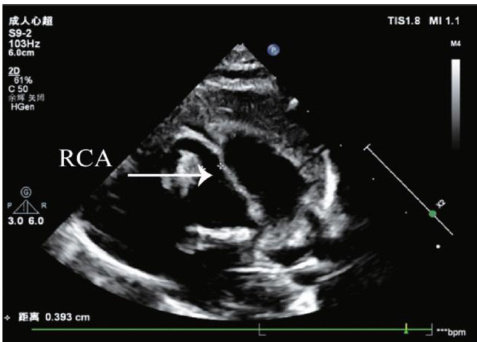

摘要 目的 探讨三维斑点追踪技术(3D-STI)评估主动脉瓣重度狭窄(AS)患者经导管主动脉瓣置换术(TAVR)后左心功能的临床价值。方法选取我院行TAVR的AS患者31例(AS组)和同期健康体检者31例(对照组),应用二维超声心动图获取左室舒张末内径(LVEDD)、收缩末内径(LVESD)、左室质量指数(LVMI),3D-STI获取左室整体主应变(GPS)整体纵向应变(GLS)整体圆周应变(GCS)整体径向应变(GRS)、三维射血分数(3D-LVEF),比较对照组与AS组,以及AS组术前与术后1、3、6个月上述参数的差异。结果与对照组比较,AS组术前LVEDD、LVESD、LVMI均升高,3D-LVEF、GPS、GLS、GCS、GRS均降低,差异均有统计学意义(均 P<0.001 ;AS组术后6个月LVMI仍升高,GPS、GLS、GCS仍降低,差异均有统计学意义(均 P<0.001 )。AS组术前、术后不同时间LVEDD、LVESD、LVMI、3D-LVEF、GPS、GLS、GRS、GCS比较差异均有统计学意义(均 P<0.05 )。与术前比较,AS组术后1个月LVEDD、LVMI均降低,GPS、GLS、GRS均升高,术后3个月和术后6个月LVEDD、LVESD及LVMI均降低,3D-LVEF、GPS、GLS、GRS及GCS均升高,差异均有统计学意义(均 P<0.001. );与术后1个月比较,术后3个月LVESDLVMI均降低,3D-LVEF、GPS、GLS、GCS均升高,术后6个月除LVEDD差异无统计学意义外,其余参数比较差异均有统计学意义(均 P<0.001 );与术后3个月比较,术后6个月LVMI进一步降低,GPS、GLS、GRS、GCS均进一步升高,差异均有统计学意义(均 P<0.001 )。结论AS患者TAVR后左心功能呈阶段性改善,3D-STI能早期、准确地评估其变化,具有一定的临床价值。